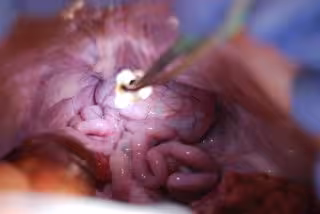

Una operación con el dispositivo Rutilight del Hosp.Germans Trias i Pujol

HOSPITAL GERMANS TRIAS I PUJOL

Bautizado como Rutilight, el sistema de iluminación --desarrollado a través de la 'spin-off' Swan Medical-- permite acercar más la luz que en los sistemas tradicionales y ponerla donde se necesita para trabajar, lo que "facilita la labor de los cirujanos y permite afrontar y resolver eventuales complicaciones", han añadido.